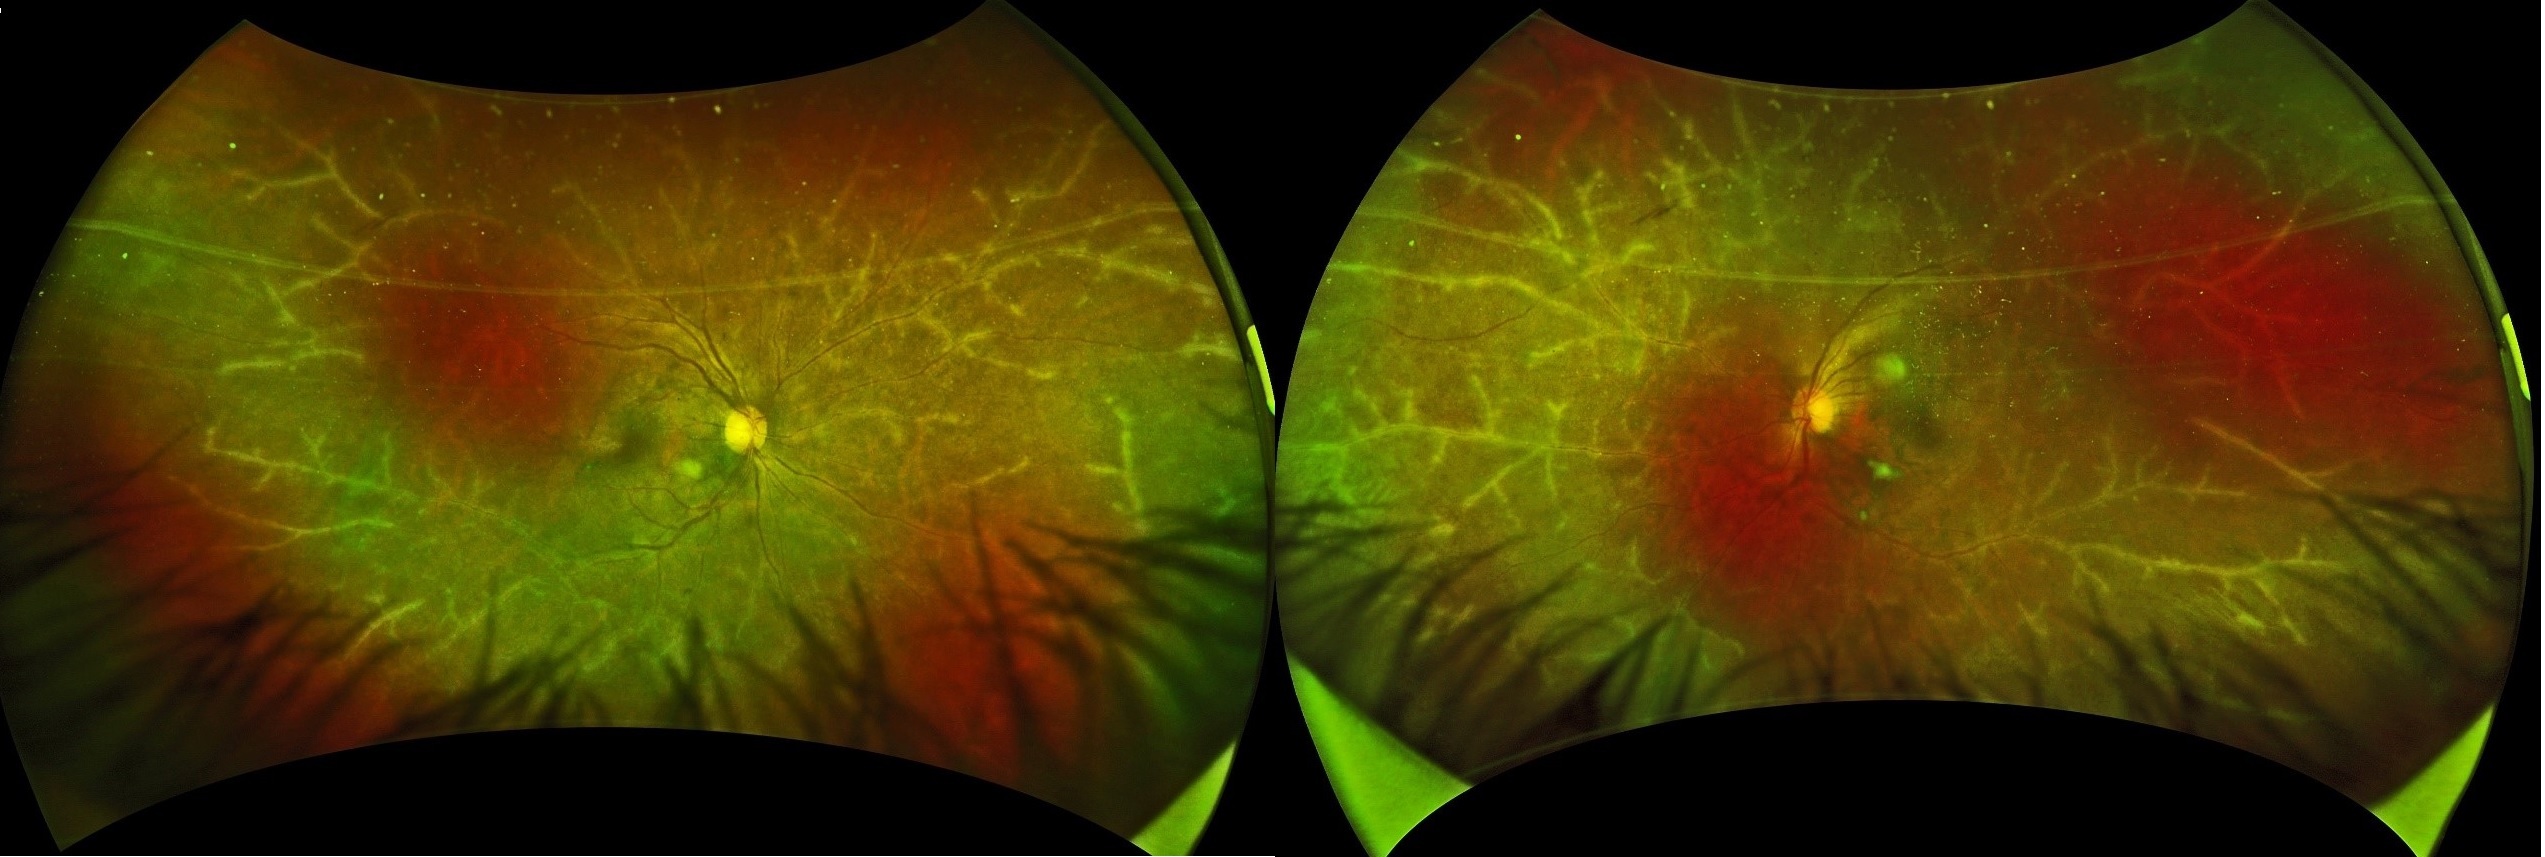

Minimally Invasive Drug and Cell Delivery Systems Targeting the Posterior Segment of the Eye by Hirokazu Kaji 2023.03.03